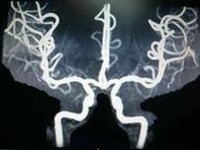

血管收縮血管收縮,亦即血管收窄,是指體內血管管腔收窄,這會造成血壓的上升。它的相反過程稱為血管舒張。

血管收縮圖血管收縮圖臨床套用局麻時常在麻藥溶液中加入血管收縮劑,這是由於口腔頜面部血運豐富,對局部麻醉藥吸收快。為延緩吸收,加強鎮痛效果,延長局麻時間,降低毒性反應,以及減少術區出血,使術野清晰,在局麻藥溶液中加入血管收縮劑是完全必要的。